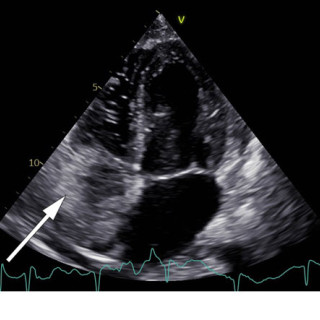

En mann i 50-årene ble innlagt etter residiverende episoder med brystsmerter. På innleggelsesdagen synkoperte han fra sittende stilling. Utredningsforløpet avdekket en diagnose som er sjelden, men med klassiske symptomer og funn. En mann i 50-årene med kjent hypertensjon, velregulert med kandesartan (tabletter, 8 mg × 1), ble henvist til akuttmottaket på grunn av episoder med brystsmerter. Han var normalvektig, hadde aldri røykt og hadde ingen rusbrukslidelse, og det var ingen kjent diabetes, hyperkolesterolemi, opphopning av hjertesykdom eller prematur hjertedød i familien. Over en periode på...